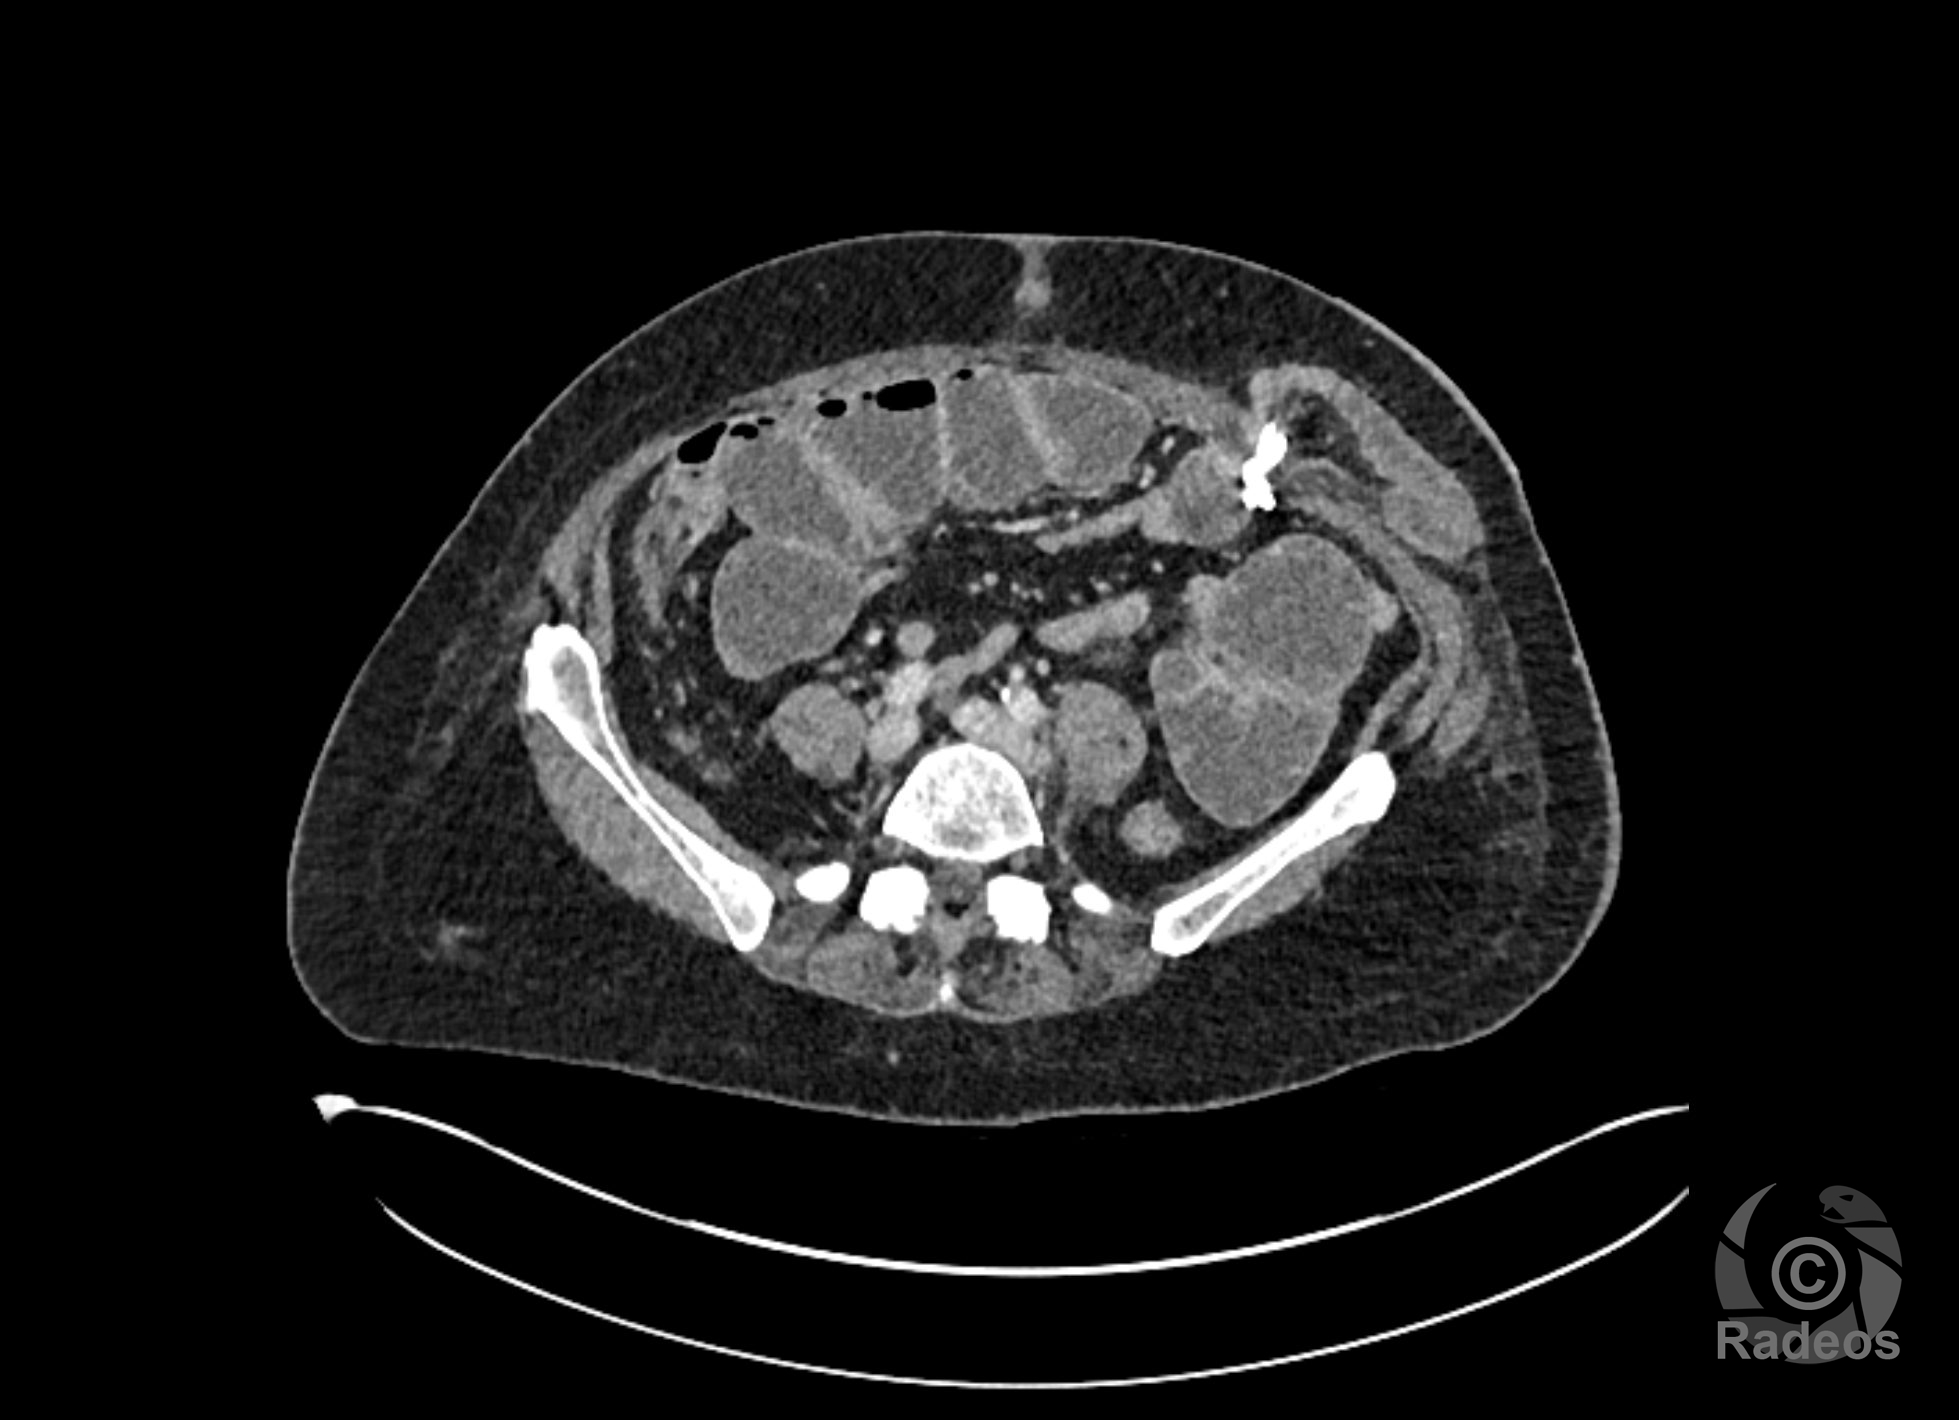

LE CAS DU MOMENT

Aspect IRM d'une fibromatose profonde de la paroi abdominale. Découverte fortuite d'un angiome hépatique gauche.